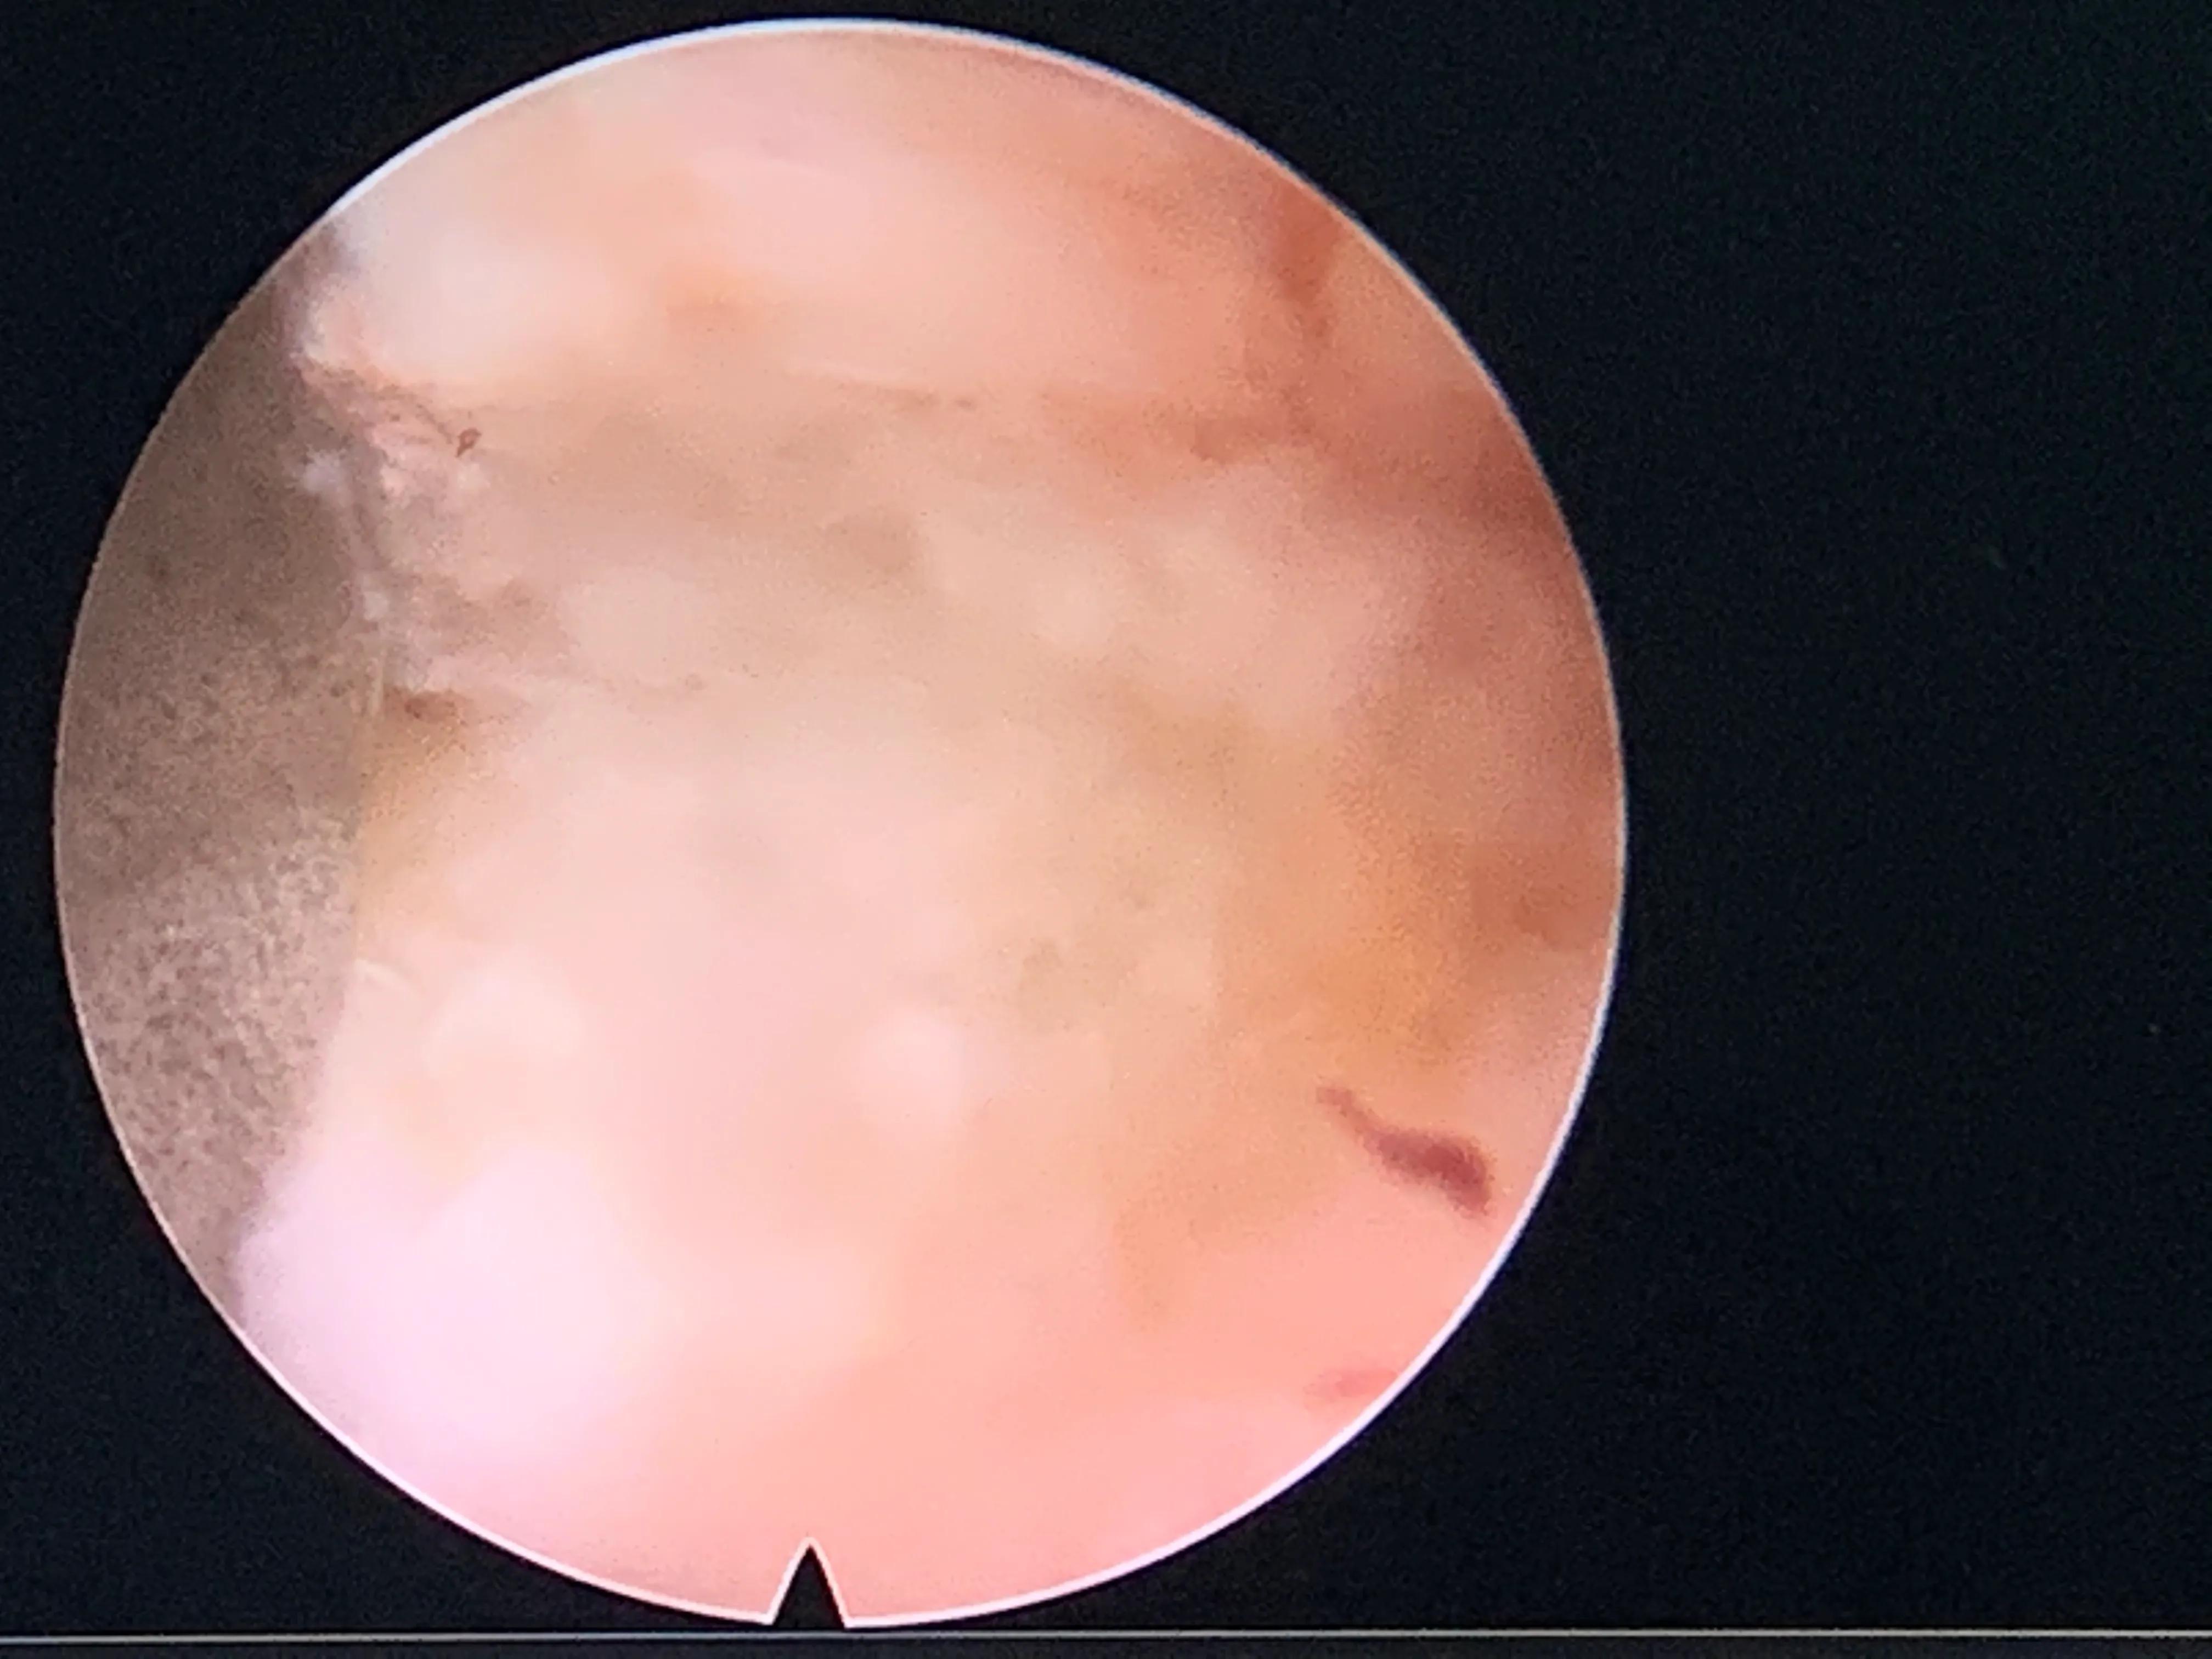

上关节突后外侧的软组织

环锯开窗

显露间盘